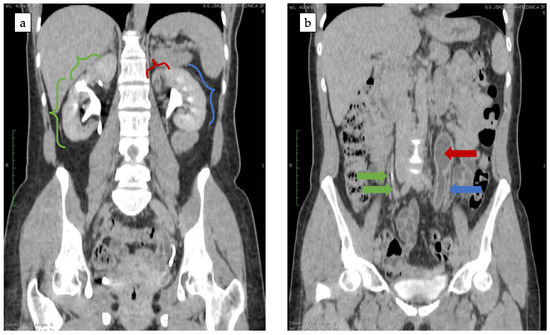

2.1. Case Study No. 1

2.2. Case Study No. 2